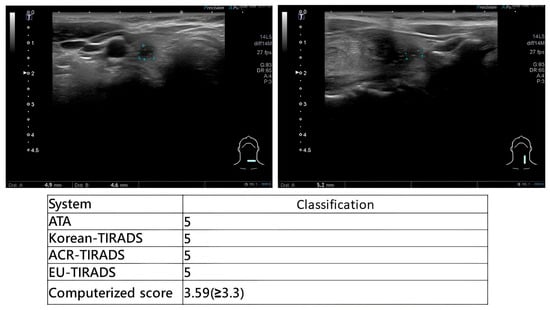

Comparative Diagnostic Performance of Ultrasound-Based Risk Stratification Systems in Thyroid Nodule Evaluations by Otolaryngologists

Background/Objectives: Thyroid nodules are a prevalent condition with a high incidence rate of malignancy. Ultrasound (US)-based risk stratification systems have become widely utilized for the evaluation of thyroid nodules, including the American Thyroid Association (ATA) guidelines, the American College of Radiology Thyroid Imaging [...] Read more.

Background/Objectives: Thyroid nodules are a prevalent condition with a high incidence rate of malignancy. Ultrasound (US)-based risk stratification systems have become widely utilized for the evaluation of thyroid nodules, including the American Thyroid Association (ATA) guidelines, the American College of Radiology Thyroid Imaging Reporting and Data System (ACR-TIRADS), the Korean Society of Thyroid Radiology system (K-TIRADS), and the European Thyroid Association system (EU-TIRADS). Our institution has developed a real-time computerized score for evaluating thyroid nodules. This study aims to systematically compare the diagnostic performance of these systems when applied in real time by otolaryngologists, who integrate dynamic US imaging with physical examination. Methods: Patients with thyroid nodules who underwent US evaluation, US-guided fine-needle aspiration cytology (FNAC), and subsequent thyroidectomy were included. During each examination, otolaryngologists performed real-time risk categorization according to five US-based systems, with immediate scoring based on dynamic sonographic findings. Results: From April 2021 to November 2023, 130 patients were enrolled. For categories 4 and 5, the ATA guidelines had a sensitivity of 96.6% (95% CI: 87.3–100%), specificity of 78.9%, (60.6–97.3%) PPV of 84.6% (70.7–98.5%), NPV of 93.7% (81.9–100%), and accuracy of 88.1% (78.3–97.9%). The sensitivity of the ACR-TIRADS was 95.6% (87.3–100%), the specificity was 78.9% (60.6–97.3%), the PPV was 84.6% (70.7–98.5%), the NPV was 93.7% (81.9–100%), and the accuracy was 88.1% (78.3–97.9%). Both the K-TIRADS and the EU-TIRADS had sensitivities of 95.6% (87.3–100%), specificities of 78.9% (60.6–97.3%), PPVs of 84.6% (70.7–98.5%), NPVs of 93.7% (81.9–100%), and accuracies of 88.1% (78.3–97.9%). The computerized score (>3.3 considered malignant) and TBSRTC (Category 5 or 6) both had sensitivities of 73.9% (56.0–91.9%), specificities of 100%, PPVs of 100%, NPVs of 76.0% (59.3–92.7%), and accuracies of 85.7% (75.1–96.3%). Conclusions: Otolaryngologists can achieve highly accurate diagnostic performance when applying standardized ultrasound-based risk stratification systems, and a real-time computerized scoring system provides highly specific supplemental value for immediate clinical decision-making. Full article

Show Figures

Figure 1